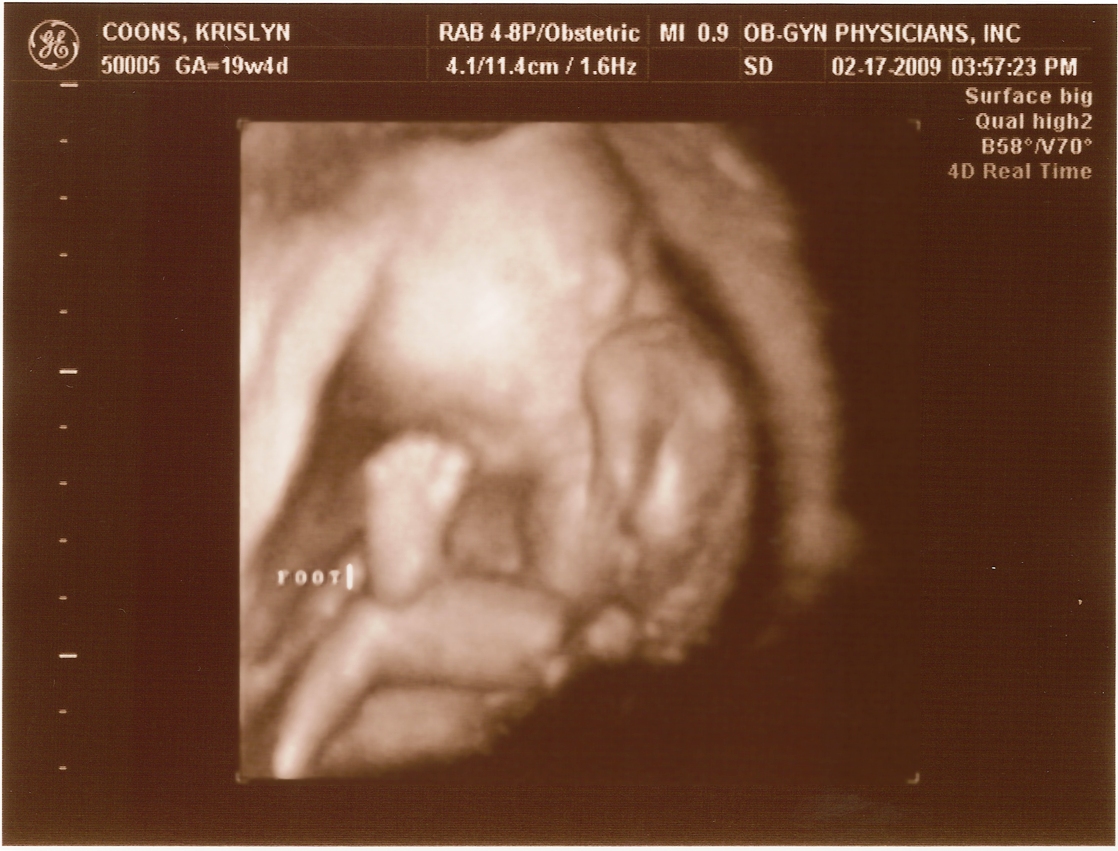

20 weeks -

Arm & Head

20 weeks